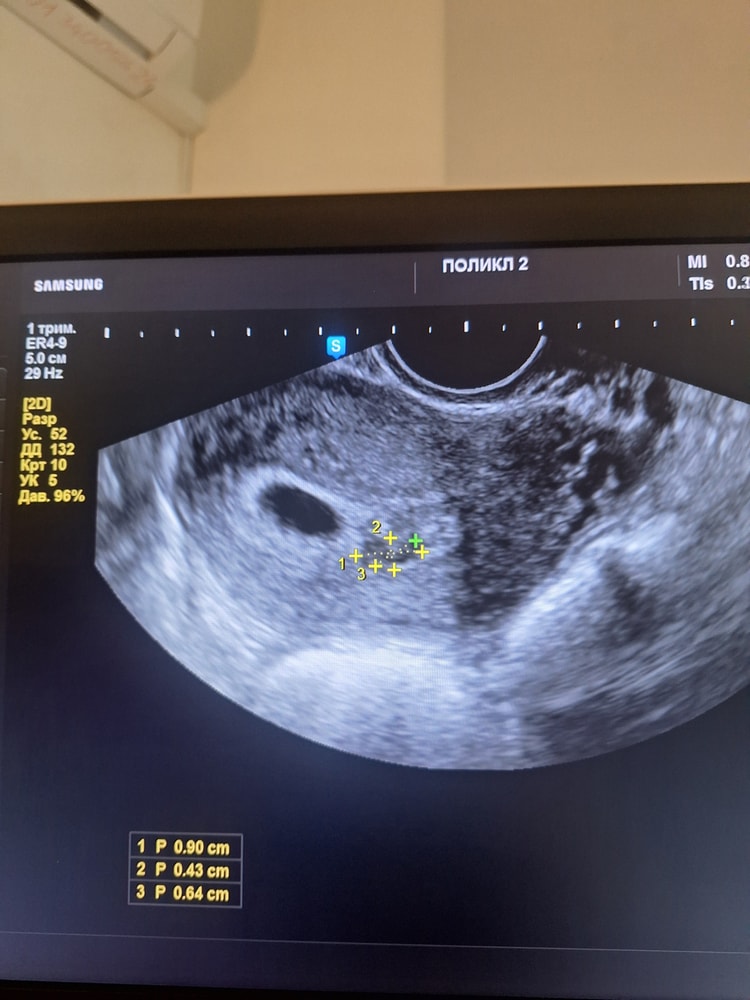

По УЗИ врач сказал маленькая гематома ретрохориальная, типа она уже заживающая и ничего страшного. Фото прилагаю.